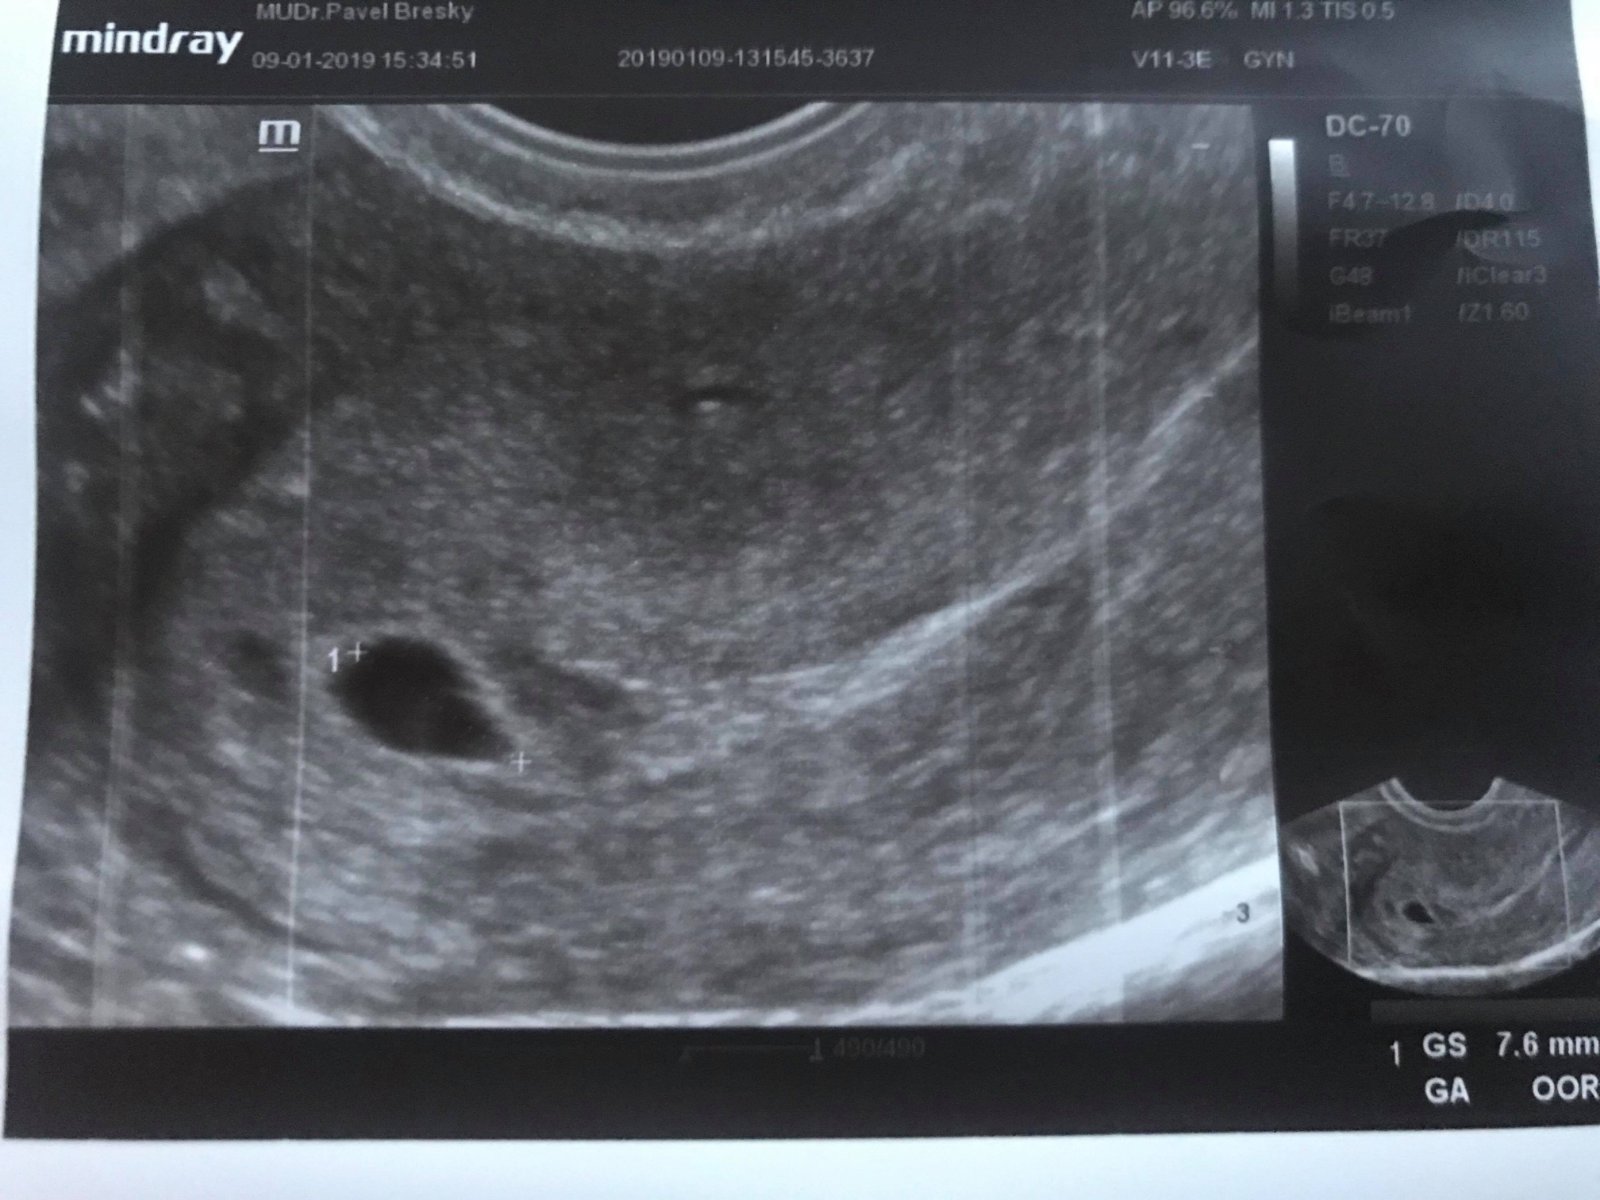

Ahojky, pravděpodobně kvůli těhu jsem dostala zánět močáku a doktor mi nasadil kombinaci Furolin a biseptol pro děti. Nevěděla jsem v té době že jsem těhotná a léky podstivě dobrala, protože se mi zánět už poněkolikáté vrátil :(. Byla jsem včera na úplně první kontrole a Dr. vypočítal, že bych měla být v 8, skoro 9 týdnu...pak ale přišlo na ultrazvuk a byl na něm vidět jenom váček, bez ničeho uvnitř..prostě jenom černá prázdná bublina velikosti 7,6mm. Doktor říkal, že to rozhodně neodpovídá velikosti jakou by to mělo mít, že už by mělo být vše hezky vidět. Nedokázal mi říct, jestli je to živé těhotenství nebo ne :/ Za dva týdny máme jít na kontrolu a strašně se bojím a nevím co čekat... :/. Poslední MS jsem měla 13.listopadu 5 dní a cca někdy za týden pak ovu.

Připojuju fotku UTZ, jakákoliv zkušenost pomůže :/